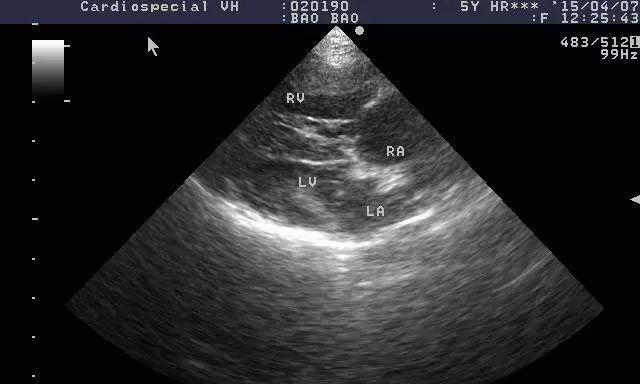

7.诊断与治疗:早期发现与有效干预